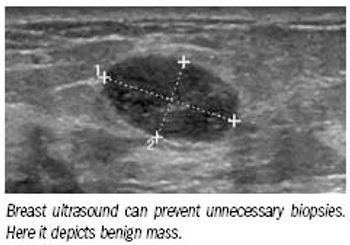

Breast ultrasound is having its moment. Multiple scientific presentations at the 2009 RSNA meeting showed how careful use of ultrasound could allow imagers to so precisely characterize lesions that women could avoid biopsies.